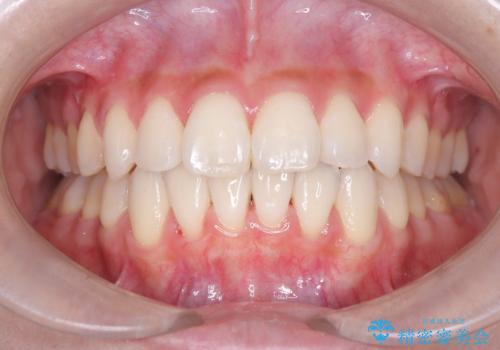

【インビザライン】前歯のねじれを治したい

- 前歯のガタガタを主訴に来院されました。

叢生の量は軽度でしたが臼歯の遠心移動を行い、インビザラインにて治療をしました。

叢生の改善に必要なスペースは遠心移動やIPRで作ることが可能です。今回は遠心移動をメインにスペースを作って叢生の改善を行いました。